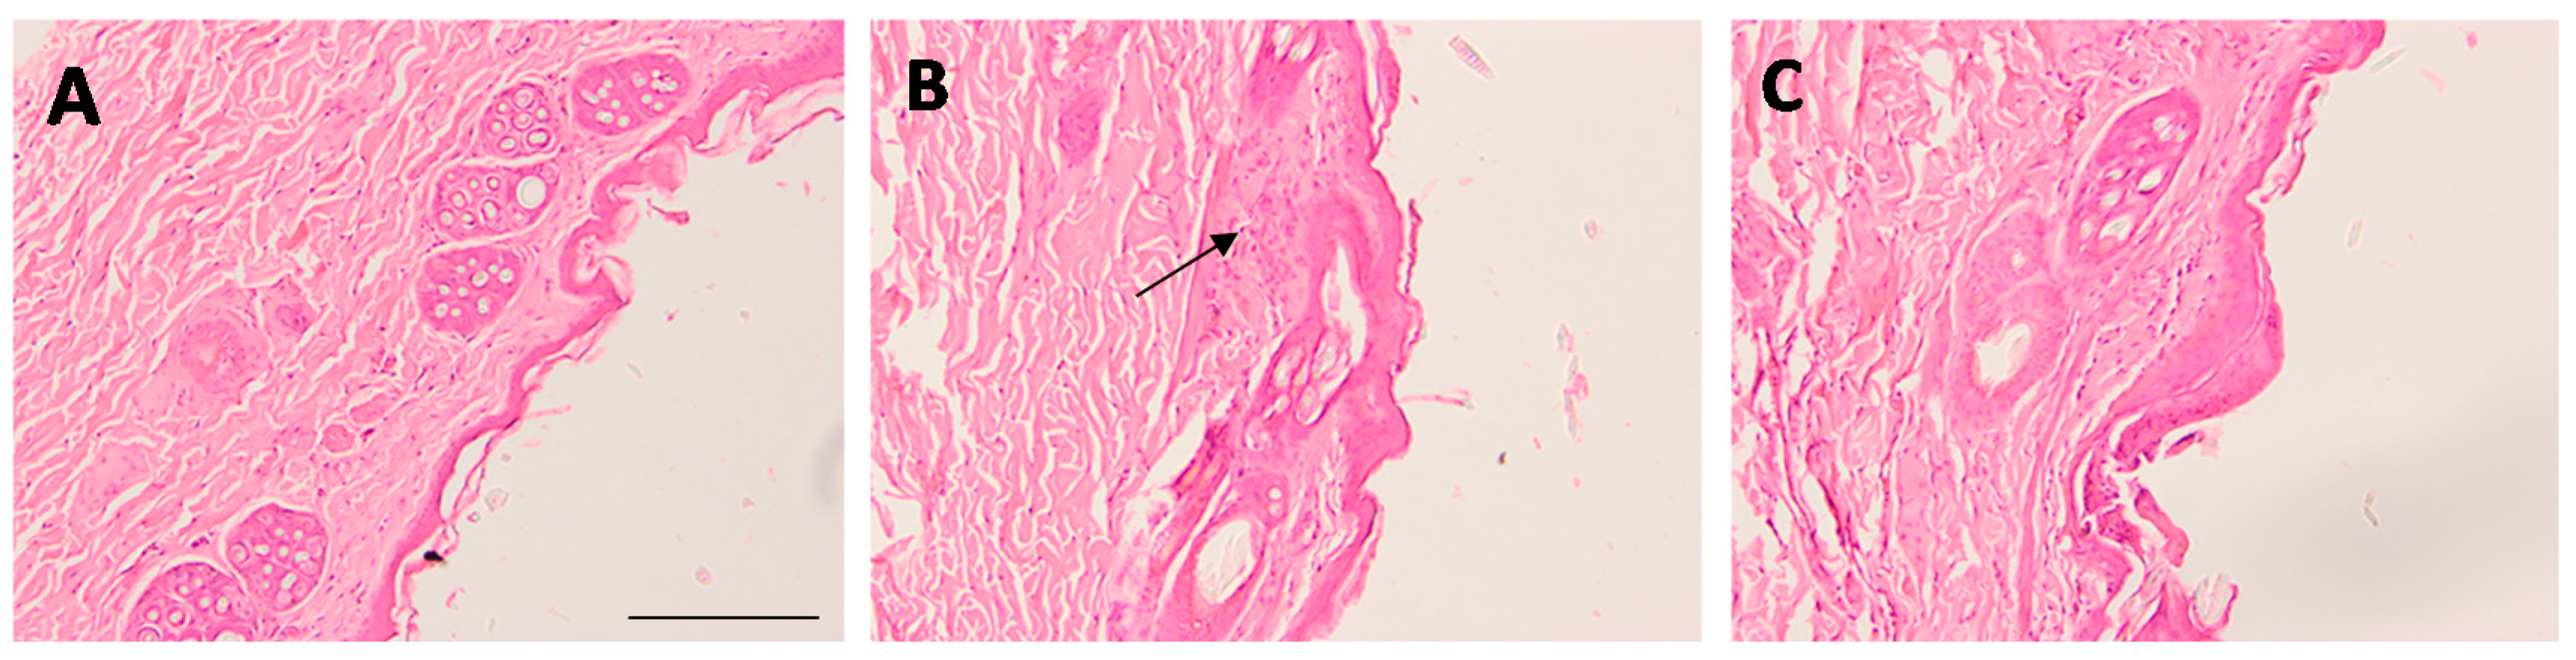

The tolerance of the formulation was evaluated using scarified rabbit skin. The blank-gel and AmB-gel were tested on New Zealand albino male rabbits (2 kg) according to the guidelines provided by the CEEA-UB. The rabbits were acclimated over a 5-day period before the study and were classified into three groups (n = 3/group): Group A (Blank-gel), Group B (Skin scarified-control group), and Group C (AmB-gel). The surrounding area of the dorsal trunk was shaved with clippers where a square was drawn for scarification with a razor before beginning the assay. After 30 min, a volume of 0.5 mL of either Blank-gel or AmB-gel was topically applied on the scarified skin of each corresponding group while group B was not exposed to any treatment. This area was protected with gauze and secured with hypoallergenic sticking plaster for 48 h. The signal of edema and erythema were determined after 24 h and 48 h of exposure. Both scores were established according to the degree of severity and the primary irritation index value was calculated. The treatment was classified according the reported specifications: “nonirritant” (<0.5), “irritant” [2,3,4,5], or “highly irritant” [5,6,7,8,23]. Afterwards, the rabbits were anesthetized and euthanized with sodium pentobarbital.

For histological analysis, the samples of back skin from the rabbits were cut and set up for 24 h in 4% buffered formaldehyde at room temperature. After fixation, all samples were paraffin embedded in paraffin blocks, cut into 5 µm sections, and mounted on microscope slides. Afterwards, the samples were stained with hematoxylin and eosin and finally viewed on blind coded samples under a light microscope (Olympus BX41 and Olympus XC50 camera) with 100× magnification for the evaluation of the tissue structure.

3.10. In Vivo Tolerance Study on Scarified Rabbit Skin by Draize Assay and Histological Analysis

The Draize test was carried out in order to evaluate the skin irritation potential of AmB-gel. After 48 h, the resulting primary irritation index value for Blank-gel and AmB-gel was 0.38 and 0.45, respectively. This result indicates that both blank-gel and AmB-gel are nonirritants.

Regarding the histological evaluation, micrographs revealed that scarification caused histological alterations and the presence of nonspecific inflammatory cells in the skin (Figure 11B) while the topical application of Blank-gel (Figure 11A) and AmB-gel (Figure 11C) notably repaired these alterations, resulting in a less pronounced inflammatory process than that of the control group (Figure 11B).

Finally, the tolerability of the formulation was evaluated by in vivo model using scarified rabbit skin in order to simulate the damage of the skin barrier caused by the fungal infection. The irritation index values for AmB-gel and Blank-gel were less than 0.5 and can therefore be classified as nonirritant formulations. This result was consistent with histological analysis, which showed that both formulations did not cause any alteration of the skin architecture but, on the contrary, they actually repaired the ulcerated skin. According to this finding the ability of P407 to reduce wounds in burn patients while simultaneously stimulating the proliferation of collagen fibers, consequently increasing scarring and generating new tissue, have all been reported in previous studies [44]. In conjunction, these effects might favor the healing and alleviation of wounds caused by Candida. In conclusion, AmB-gel represents a promising therapeutic option to treat these types of infections via dermal application.

Figure 11. Optical microscopic images of skin. Blank-gel (A), skin-scarified control group (B), and AmB-gel (C). Hematoxylin and eosin stains nuclei blue/black while keratin and cytoplasm are stained red. Scale bar = 200 μm.